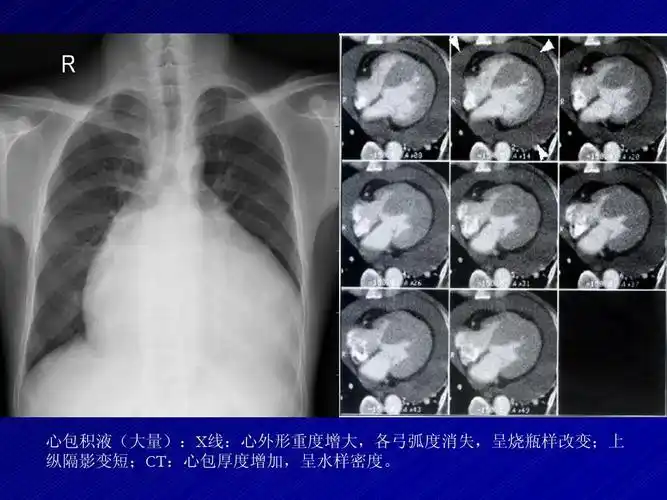

梨形心靴形心烧瓶心这也样看平片想不会都难